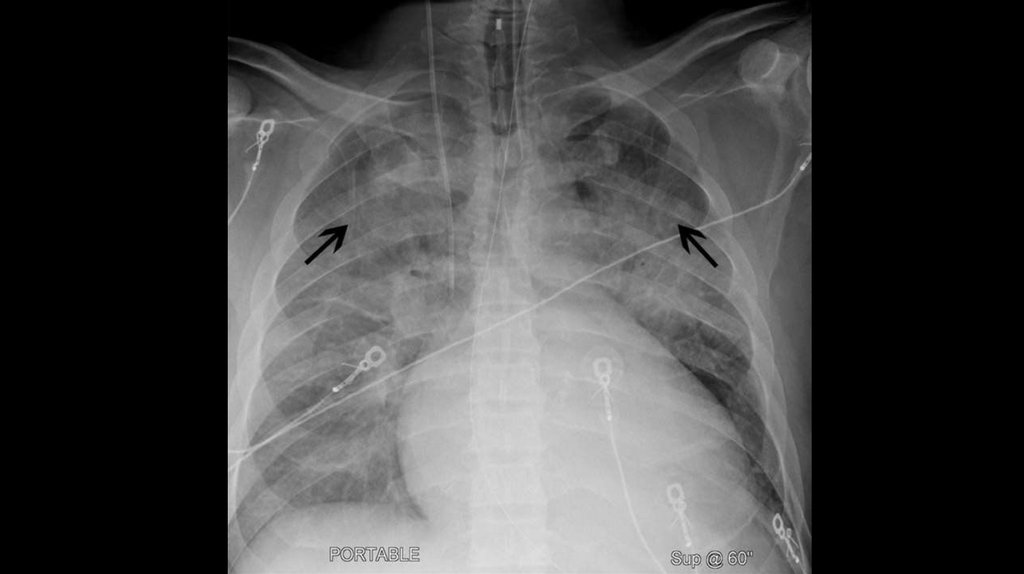

16. Рентген грудной клетки

Главное внимание при подозрении на ХСН следует уделять

кардиомегалии (кардио-торакальный индекс >50%) и венозному

легочному застою. Кардиомегалия – свидетельство вовлеченности

сердца в патологический процесс. Наличие венозного застоя и его

динамика могут быть использованы для характеристики тяжести

заболевания и служить объективным критерием эффективности

терапии.